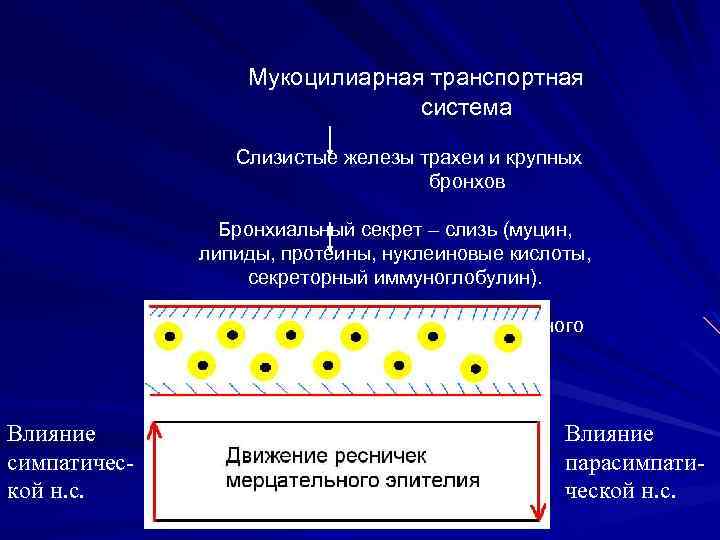

Мукоцилиарная транспортная система Слизистые железы трахеи и крупных бронхов Бронхиальный секрет – слизь (муцин, липиды, протеины, нуклеиновые кислоты, секреторный иммуноглобулин). Мерцательный эпителий бронхиального дерева Влияние симпатической н. с. Влияние парасимпатической н. с.